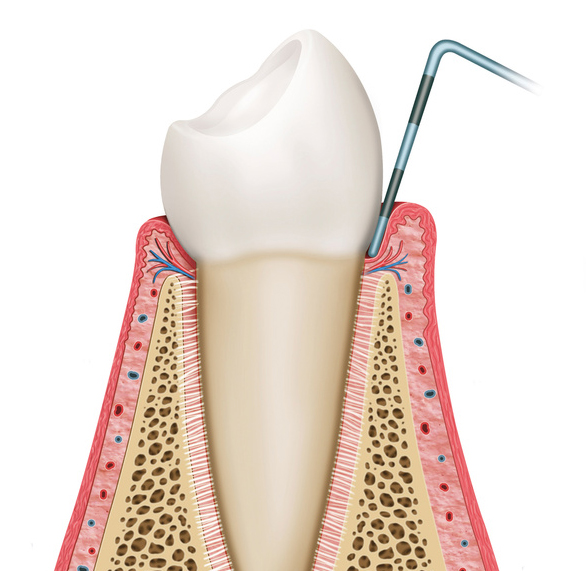

歯周病とは、歯の周りの組織(歯肉や歯槽骨など)が、プラークと呼ばれる細菌の塊内に存在する、歯周病菌に感染することによって引き起こされる、歯周組織の病気の総称を言います。

主な症状には、歯茎(歯肉)が腫れたり、出血したり、最悪な場合には歯自体が抜けてしまうこともあります。

歯周病にかかった場合、初期の段階では、ほとんど自覚症状が出ませんので、気づいていない人が多くいると思われます。

歯周疾患の原因によって、歯肉が赤くなったり、腫れたりするなどの炎症が現れます。

歯肉炎となった後、歯肉炎が進行することにより歯と歯肉の付着レベルが破壊されてしまい、歯周炎となります。

歯ぐきの腫れ・知覚過敏が起こります。